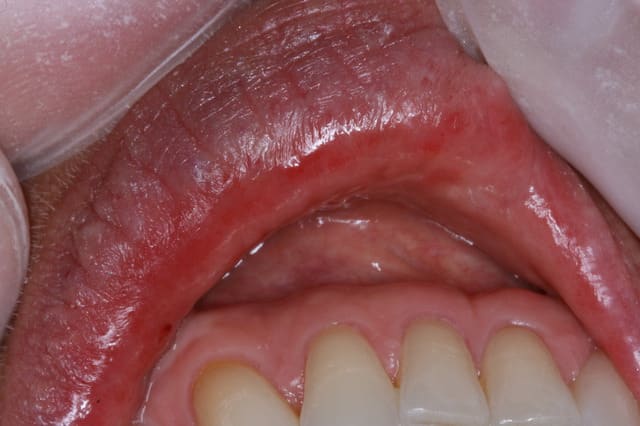

Patiente mi-cinquantaine , prend anti-hypertenseur (amilodipine et apo-hydro) ainsi que supplément calcium et vit D..

Depuis une semaine sens rugeux bout de la langue et intérieurs des lèvres. Dit avoir plus de salive (flot salivaire augmenté)

Rougeur intérieur des lèvres

rien en périphérie peau vermillon de la lèvre, seulement muqueuse interne

...seules lèvres touchées ?

un peu le bout de la langue...

augmentation du flot salivaire

plus assoiffé, boit plus